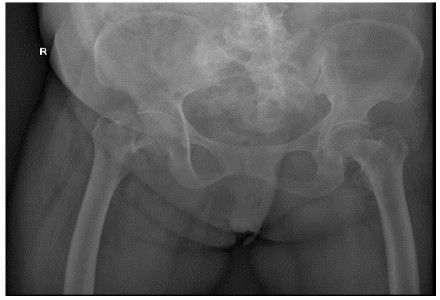

Total hip replacement was performed for her and she was allowed to walked weight-bearing with the help of a walker, 1 week later she was discharged from the hospital (Figure 4).

Figure 4: Case 1 hip replacement

FNS internal fixation was done for the fracture successfully. And she was permitted to sit in wheel-chair or stand on the unaffected leg within short period post-operatively (Figure 8).

Figure 8: Case 2 FNS internal fixation of femoral neck.